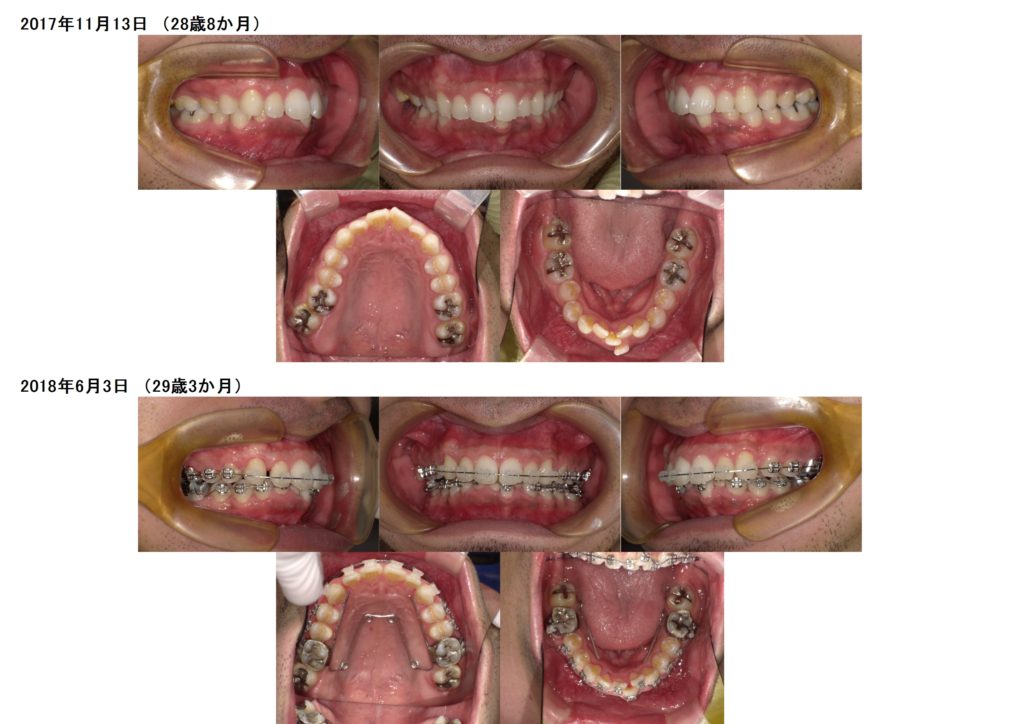

男性の方でもこのようにブラケット治療をされますよ☆

思っていたより、気づかれなかった。そんなに目立たないですね。と言われる方も多いですよ。

とってもキレイになりましたよね!!